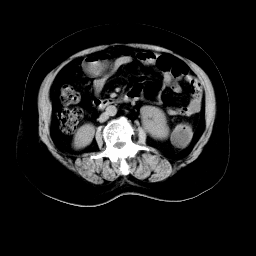

以下是引用余辉在2008-11-9 9:47:00的发言:[br]各层面均可见降结肠管壁增厚,管腔狭窄,中部层面可见管壁明显增厚区,结合病史多考虑降结肠癌,溃疡性结肠炎不除外,建议进一步检查